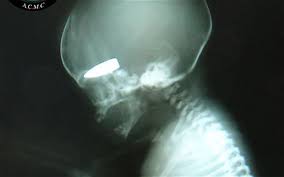

القنص والقناصة وصور لبعض القناصات السوريات